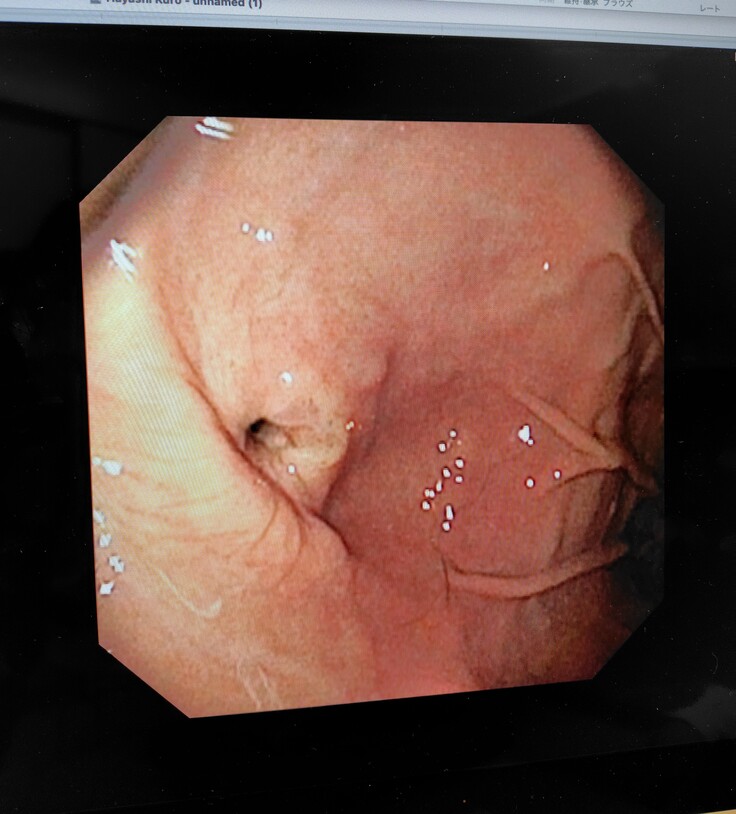

麻酔をし、内視鏡にて再度食道や胃の様子を確認され、食道の手術跡も順調に回復していたようです。胃瘻チューブの穴は医療用ボンドにて埋められそのうち塞がるとの事でした。先生に連れられて出てきてくれましたが、胃瘻チューブも取れてスッキリしてとても気分も良さそうでした😂

手術の跡もわからないくらいになり毛も生えてきてます😄胃瘻チューブ跡もわからないくらいです。

食道や胃もキレイな状態です😄本当に手術をしたのかなと思うくらい回復が早いです😄